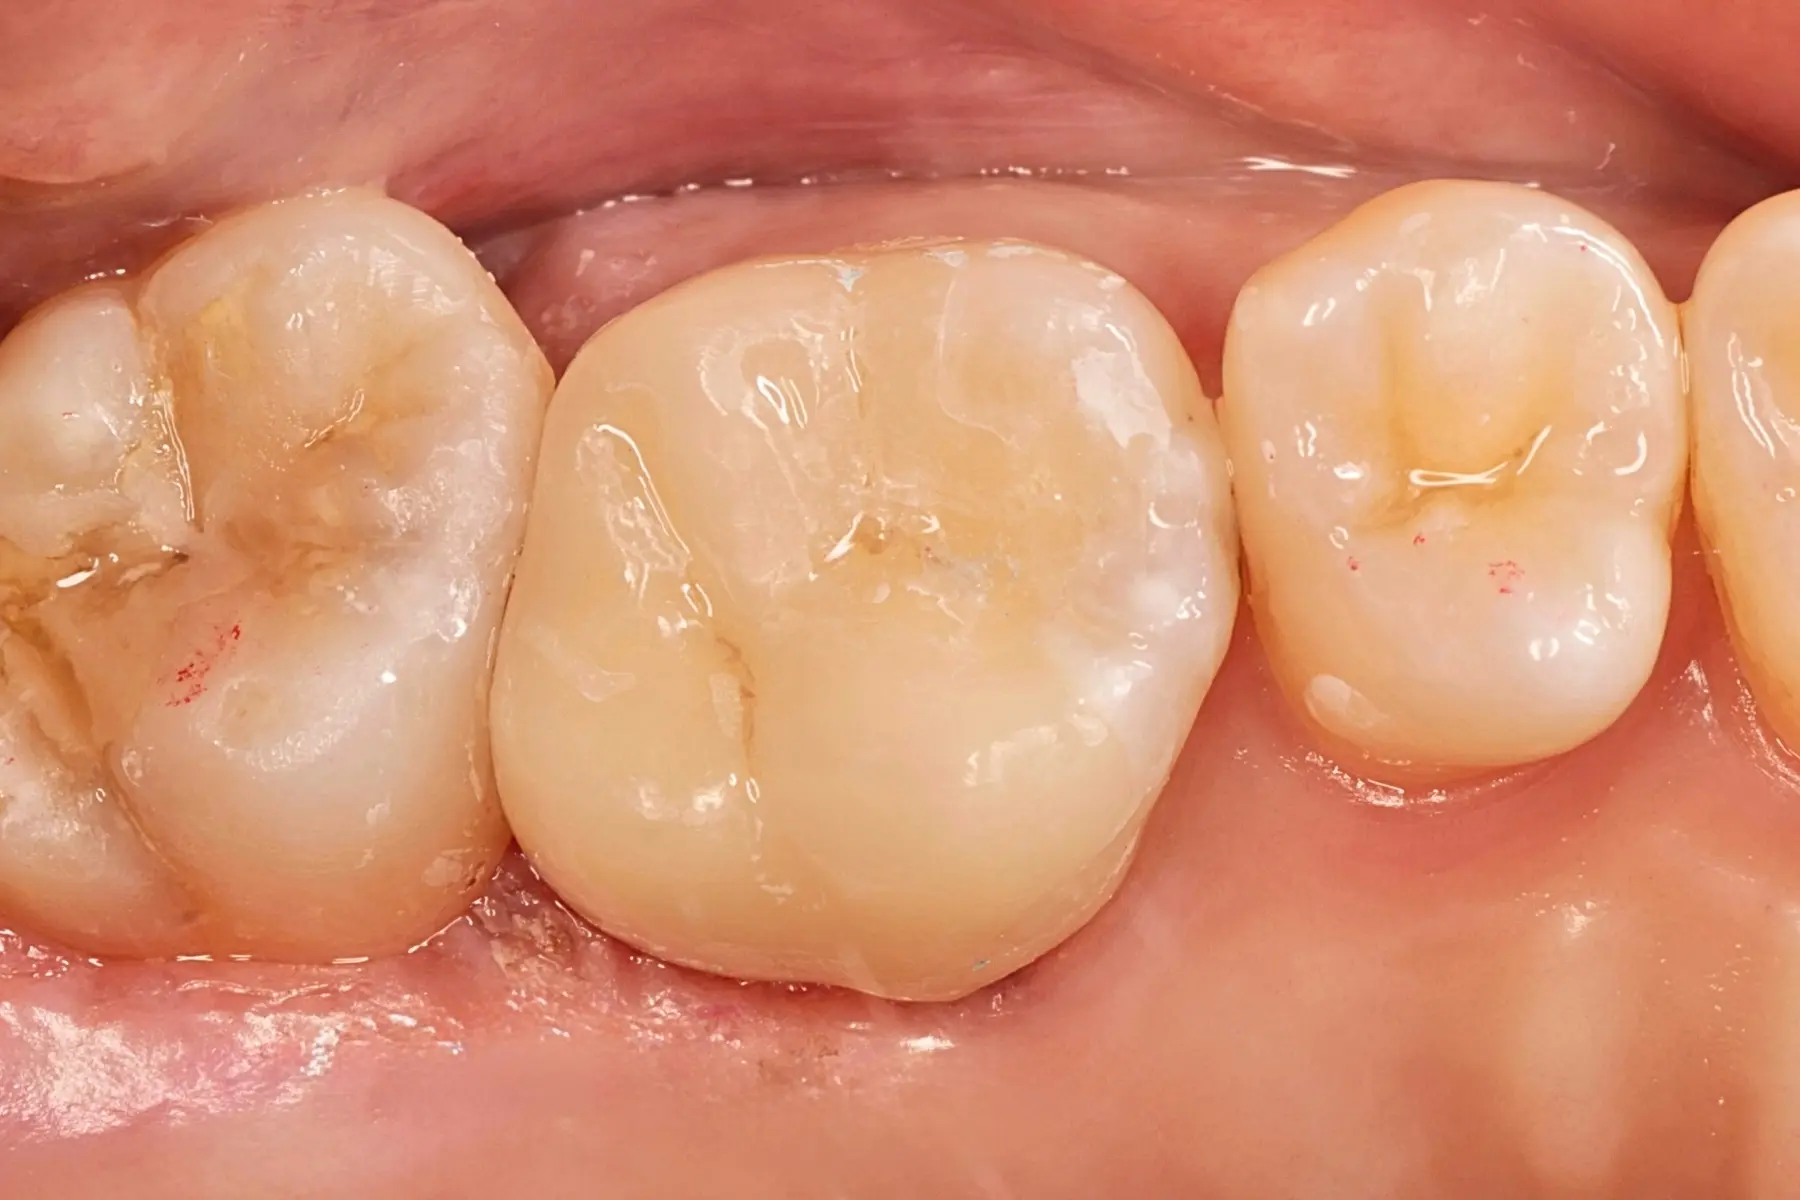

• 術前 42

術後 40

牙周治療

主治醫師

• 鍾國耀

治療時間

三次療程

主訴

牙齦紅腫出血、牙縫容易塞食物